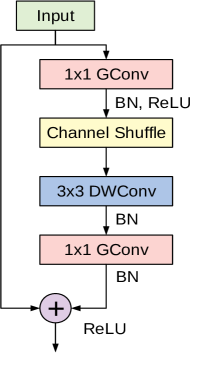

ShuffleNet is a very computationally-efficient CNN architecture that is mainly designed for mobile devices with constrained computational power [47, 43]. The architecture introduces two important operations to significantly reduce the computational cost while maintaining accuracy. The first operation is pointwise group convolutions, which can reduce the computational complexity of the convolutions. The second operation consists of shuffling the channels, which assists the information flow across feature channels.

The cornerstone of the ShuffleNet model is the ShuffleNet unit depicted in Figure 5. It is a bottleneck residual module in which the convolutional layer is replaced by a depthwise separable convolution as in [42]. Also, the first convolutional layer is replaced by a pointwise group convolution followed by a channel shuffle operation. The second pointwise group convolutional layer is used to retrieve the channel dimension to match the left path of the unit. The overall ShuffleNet network is composed of a stack of these units grouped into three different stages along with other conventional convolution and pooling layers.

In this study we adopt the recent variant of the ShuffleNet architecture. The original model uses an RGB-input of , however, we found that an input resolution of works better for the considered datasets.